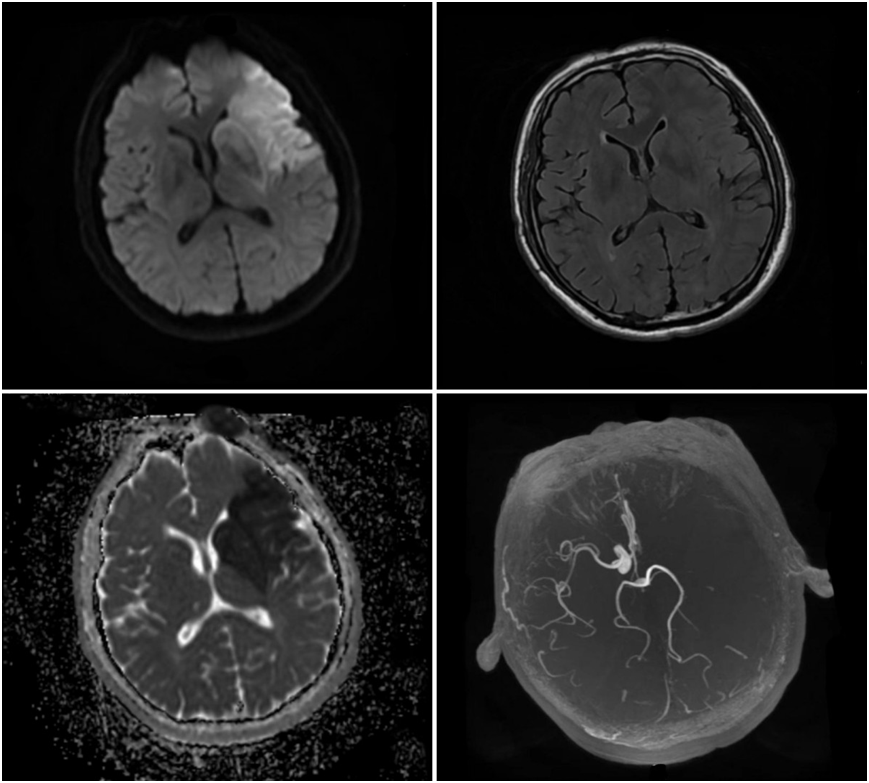

该患者因“突发意识不清伴右侧肢体活动不灵7小时”收治于烟台山医院北院神经内一科。入院后颅脑磁共振检查提示大面积脑梗死(图1),北院神经内一科王英主任医师带领团队给予患者抗栓、降脂、改善侧支循环治疗。该病病情变化快,入院第二天在发现患者意识状态改变后,立即为患者复查颅脑CT,提示脑梗死较以前加重,中线结构位移明显(图2),患者被转到北院神经外科继续接受治疗,医生为其做了颅骨去骨瓣减压术+颞肌贴敷术。术后颅脑CT提示,中线结构移位较术前好转,脑室受压较以前减轻(图2)。

图1:术前颅脑MRI可见左侧颞叶大面积梗死灶,左侧大脑中动脉闭塞。

图2:次日复查颅脑CT提示脑水肿较前明显,左侧侧脑室受压,中线结构右侧移位。术后复查颅脑CT示中线结构移位较前好转,无出血等并发症。